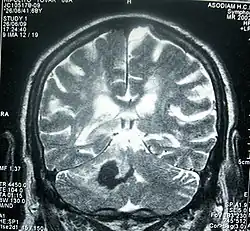

Magnetic resonance image of brain after stroke

Perinatal stroke can be diagnosed with medical imaging techniques that present the brain's image. The usage of diffusion-weighted imaging with magnetic resonance imaging is effective for early diagnosis of perinatal stroke.[18] Computerized tomography (CT) is also a commonly used diagnostic technique for this disease.[35] These medical imaging techniques can show bleeding or blockage in the brain and detect damage caused by ischemic stroke or hemorrhages to the brain tissues.[36] Magnetic resonance imaging is clinically preferred to computerized tomography as it can highlight the brain's blood flow.[35] In addition, perinatal stroke is challenging to classify on computerized tomography as the neonatal brain has higher water content.[7][36] However, in certain situations, such as the inability to transport unstable infants with severe respiratory or cardiac disorders from the intensive care unit, cranial ultrasound is used as an alternative to magnetic resonance imaging.[7] Cranial ultrasound can identify intracranial hemorrhage, intraventricular hemorrhage, and large cerebral sinus venous thrombosis along with the brain's blood flow.[7]